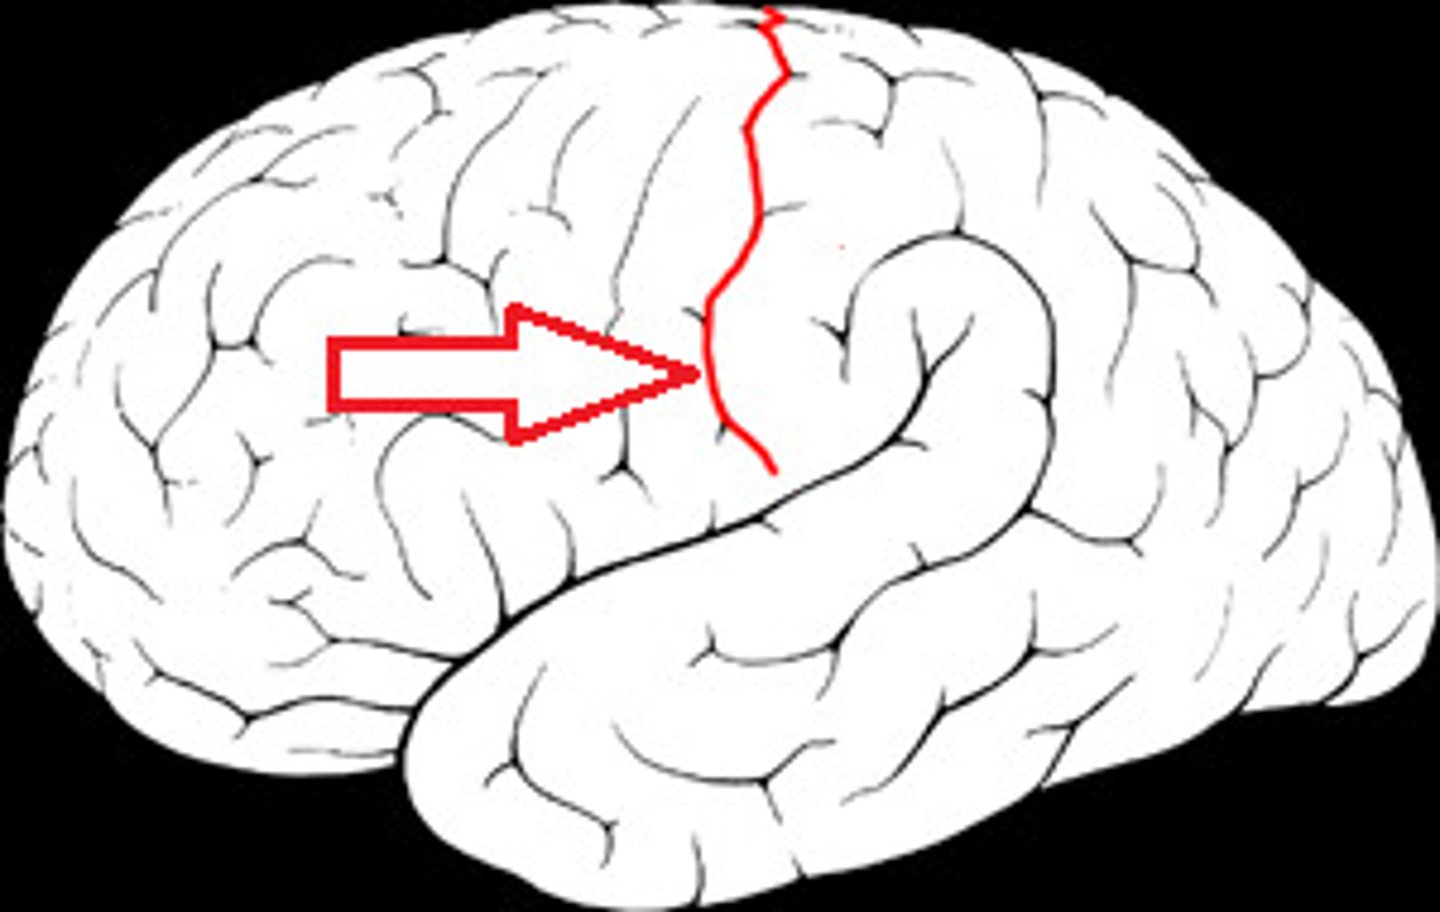

central sulcus

between postcentral and precentral gyri

longitudinal fissure

separates cerebral hemispheres

frontal lobe

associated with social cues, personality, planning, movement, emotions, and problem solving - contains primary motor cortex

precentral gyrus

primary motor cortex

parietal lobe

A region of the cerebral cortex whose functions include processing information about touch, contains primary somatosensory cortex

postcentral gyrus

primary somatosensory cortex

occipital lobe

visual center

temporal lobe

language centers, auditory processing, olfactory